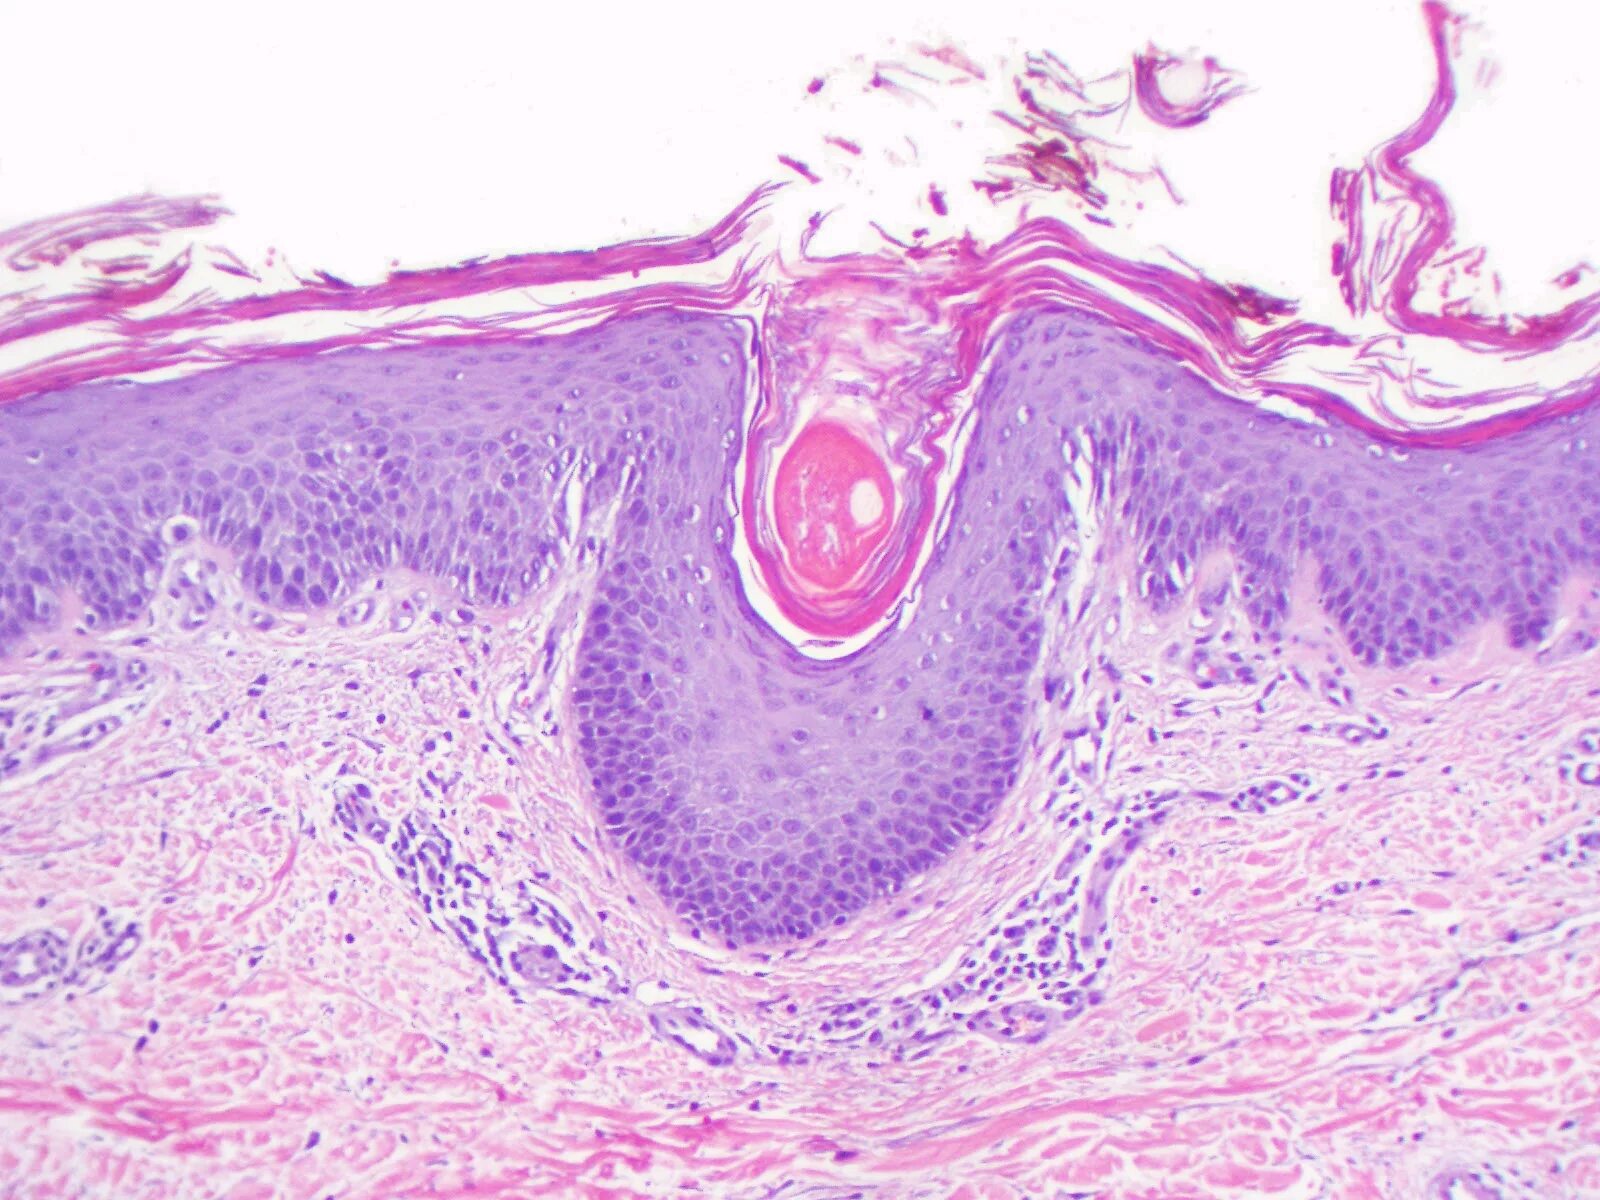

Связки гистология